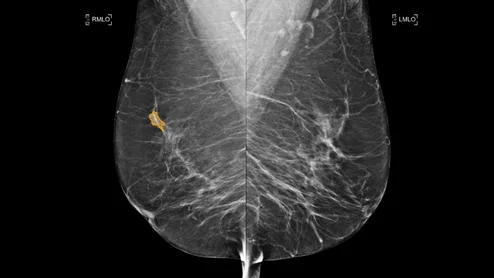

At Jefferson Health in Philadelphia, suburban screening sites have been quicker to recover than other outposts located in the city, experts write in Clinical Imaging